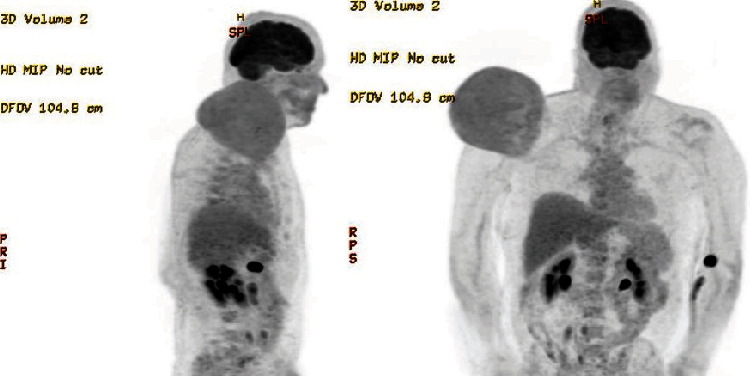

This study examines a unique case of a 61-year-old male with a 5-year history of a progressively growing mass above his right shoulder, diagnosed as a dedifferentiated pleomorphic liposarcoma. Using computerized tomography-guided core needle biopsy, the tumour was identified as intermediate to high grade. Surgical removal required preoperative radiotherapy to reduce the size of the tumour. Several unique characteristics set apart this particular case of liposarcoma: its substantial size, its unpredictable growth pattern, its absence of metastasis, and notably, its prolonged period of being untreated. This case report outlines the clinical background, diagnostic procedures, and treatment modalities employed in managing this condition, emphasizing a localized dual therapy approach combining radiotherapy and surgery. Emphasis is placed on distinguishing liposarcoma from lipoblastoma, a benign adipocyte tumour, to facilitate accurate diagnosis and appropriate treatment selection. The positive result achieved in this case could provide valuable insights for the future treatment and management of similarly sized aggressive tumours.